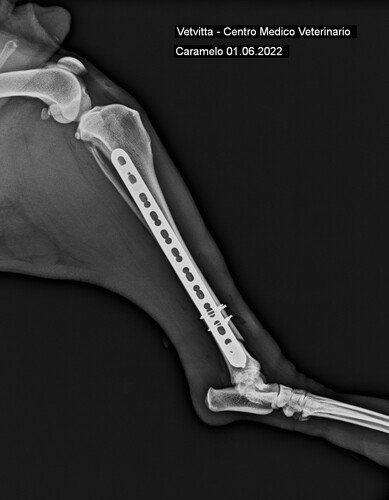

Levamos então para a Clínica Veterinária VetVitta, onde o Dr. Fábio, cirurgião e ortopedista, cuidou prontamente do Caramelo. Foram muito generosos e nos deram descontos no procedimento cirúrgico, não cobraram nem consulta nem internamento. O valor da cirurgia, incluindo medicamentos e radiografias, ficou em R$1870. Compramos também um antipulgas, porque ele estava infestado, totalizando os R$1935,50, que consta no extrato abaixo.

Radiografias Depois